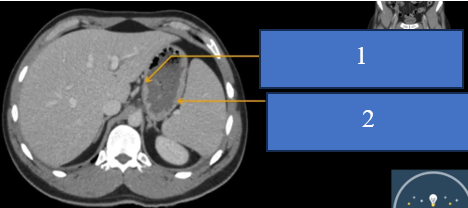

cq trong hình ?